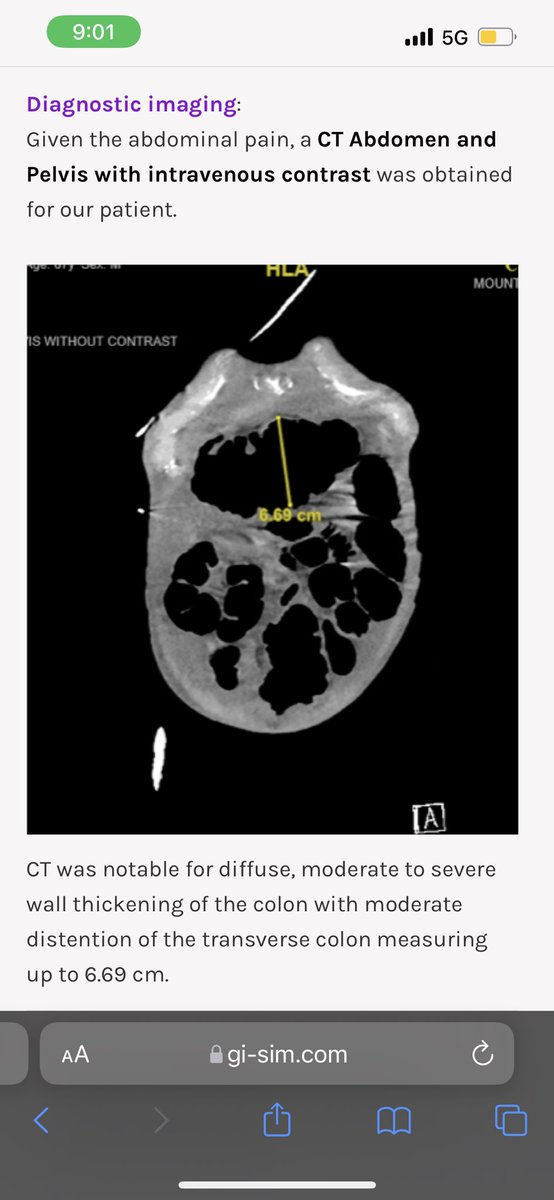

We are so excited to launch @Gisim_website • A free #Gastroenterology #Hepatology Interactive Case Based learning and teaching tool • #Meded #FOAMed Thank you @BhavanaBRaoMD @ssfarouk @Neph_SIM and all other collaborators • Check us out at GI-sim.com